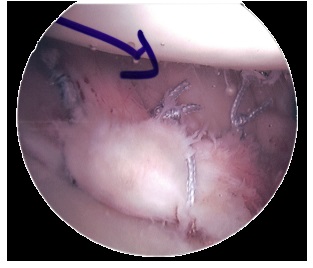

A Bankart lesion repair is usually carried out arthroscopically (hey hole surgery) under general anaesthetic. The labral tear surgery aims to repair and tighten overstretched and damaged ligaments, joint capsule and cartilage, and will also remove any cysts that have formed.

Suture anchors are placed in the bone and the torn glenoid labrum is reattached to the glenoid fossa. You can usually go home the same day, or the following day after a Bankart repair.